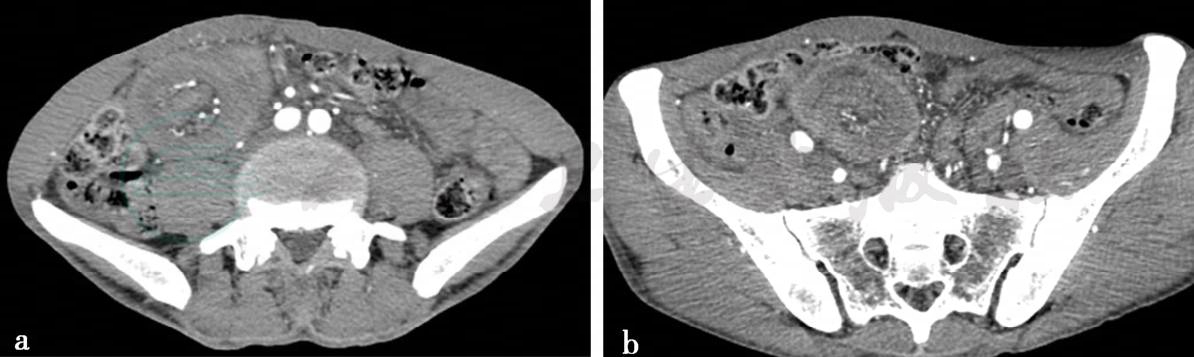

病例9:CT增强扫描图(空肠腺癌伴套叠)。

图 图1a、b,小肠双期增强CT静脉期图,分别显示不同层面。右下腹可见同心圆的套叠征象

病例9,空肠腺癌伴套叠。